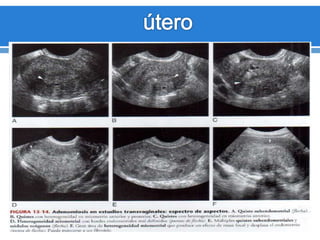

Adenomiosis

 Aumento del tamaño difuso del útero con un contorno

normal.

 Engrosamiento del miometrio posterior.

 Área afectada ligeramente mas hipoecogénica.